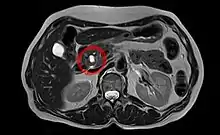

Neoplasia mucinosa papilar intraductal numa imagem por ressonância magnética.